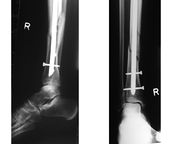

- Osteosynthesa znamená operační řešení, při kterém je kost zpevněna nejčastěji kovovým materiálem, kterým je nějaký druh nerezové oceli nebo titanu, který se po čase buď vyjme, nebo někdy i ponechá. Existuje řada metod, od jednoduchých cerkláží ocelovými dráty, přes šrouby doplněné dlahami až po nejrůznější systémy hřebování s předvrtáváním nebo bez něj (hřeb znamená navlečení nejčastěji dlouhé a duté kosti na pevný a dlouhý ocelový profil, který je na konci zafixován šrouby. Po čase se šrouby na jednom zpravidla distálním (vzdáleném) konci vyjmou, čemuž se říká dynamizace).

- Zevní fixace je navrtání speciálních hřebů někdy se závity na konci do kostních úlomků skrze kůži a jejich upevnění vně končetiny do zevního fixatéru (nejlépe si ho představíte jako stavebnici Merkur, do které zafixujete hřeby a můžete s nimi různě manipulovat a ve vhodné poloze to všechno zafixujete). Existuje řada tuzemských i zahraničních systémů, což platí pro všechny typy operačních metod.